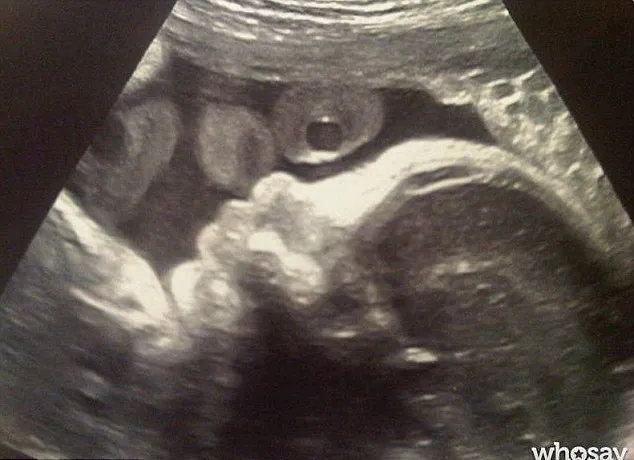

Tentu saja bisa! Pasalnya, yang dipamerkan Gerard Pique lewat Twitternya ini adalah photo scan bayi saat menjalani USG. Foto tersebut menunjukkan gambar sosok bayi yang sudah mulai terbentuk.

Bayi dalam kandungan Shakira @ dailymail.co.uk

"His first pic! #excited #cute," demikian bunyi caption yang ditulis Gerard.